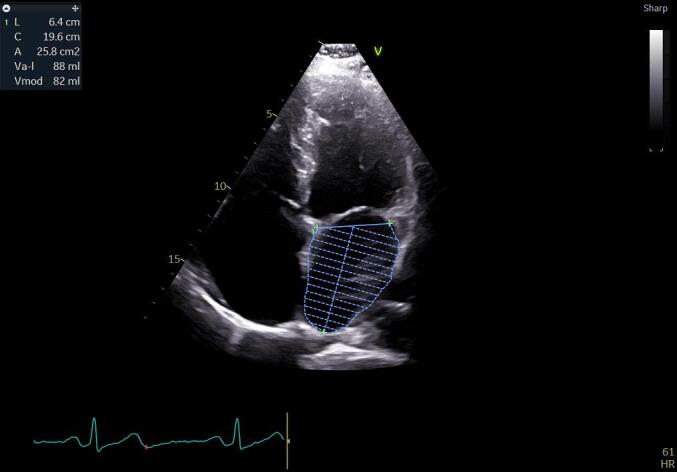

Material and methods: We performed a retrospective study in which 251 patients with AFi were included. 47 patients had an ischemic stroke before the diagnosis of AFi, at the time of diagnosis or after AFi was diagnosed. The CHA2DS2-VASc score was analyzed for all patients together with other left atrial remodeling parameters.

Results: We observed that among the patients with ischemic stroke approximately 61.70% were over 72.5 years old compared to those without stroke who presented this age in a proportion of only 44.61% (OR=2.001, P=0.0367). The CHA2DS2-VASc score had the greatest statistical impact for stroke, as expected. Patients with a CHA2DS2-VASc score >4.5 presented stroke in a proportion of 87.23% compared to CHA2DS2-VASc <4.5 who had stroke only in a proportion of 12.77% (OR=11.51, P=<0.0001). Regarding left atrial remodeling parameters, low LA ejection fraction was associated with a high percentage of stroke among patients (61.70%) compared to those with LA EF>34.5% who had stroke only in a percentage of 38.30% (OR= 2.124, P=0.0238).

Conclusions: Although the CHA2DS2-VASc score remains a good factor for predicting the association of AFi with ischemic stroke, echocardiographic parameters for the evaluation of the left atrium can be used as new risk factors for predicting the occurrence of ischemic stroke in patients with AFi.